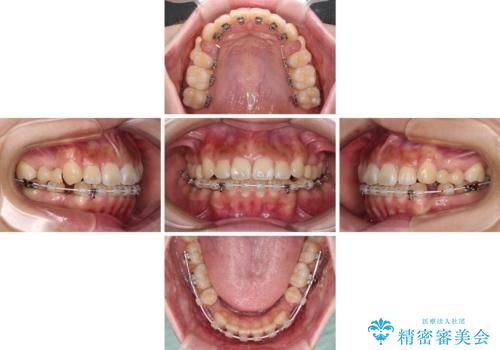

- ハーフリンガル

- 3年2ヶ月

- 30回以上

目立たない装置を希望とのことで、上顎が裏側、下顎が表側のハーフリンガル装置を用いることとしました。